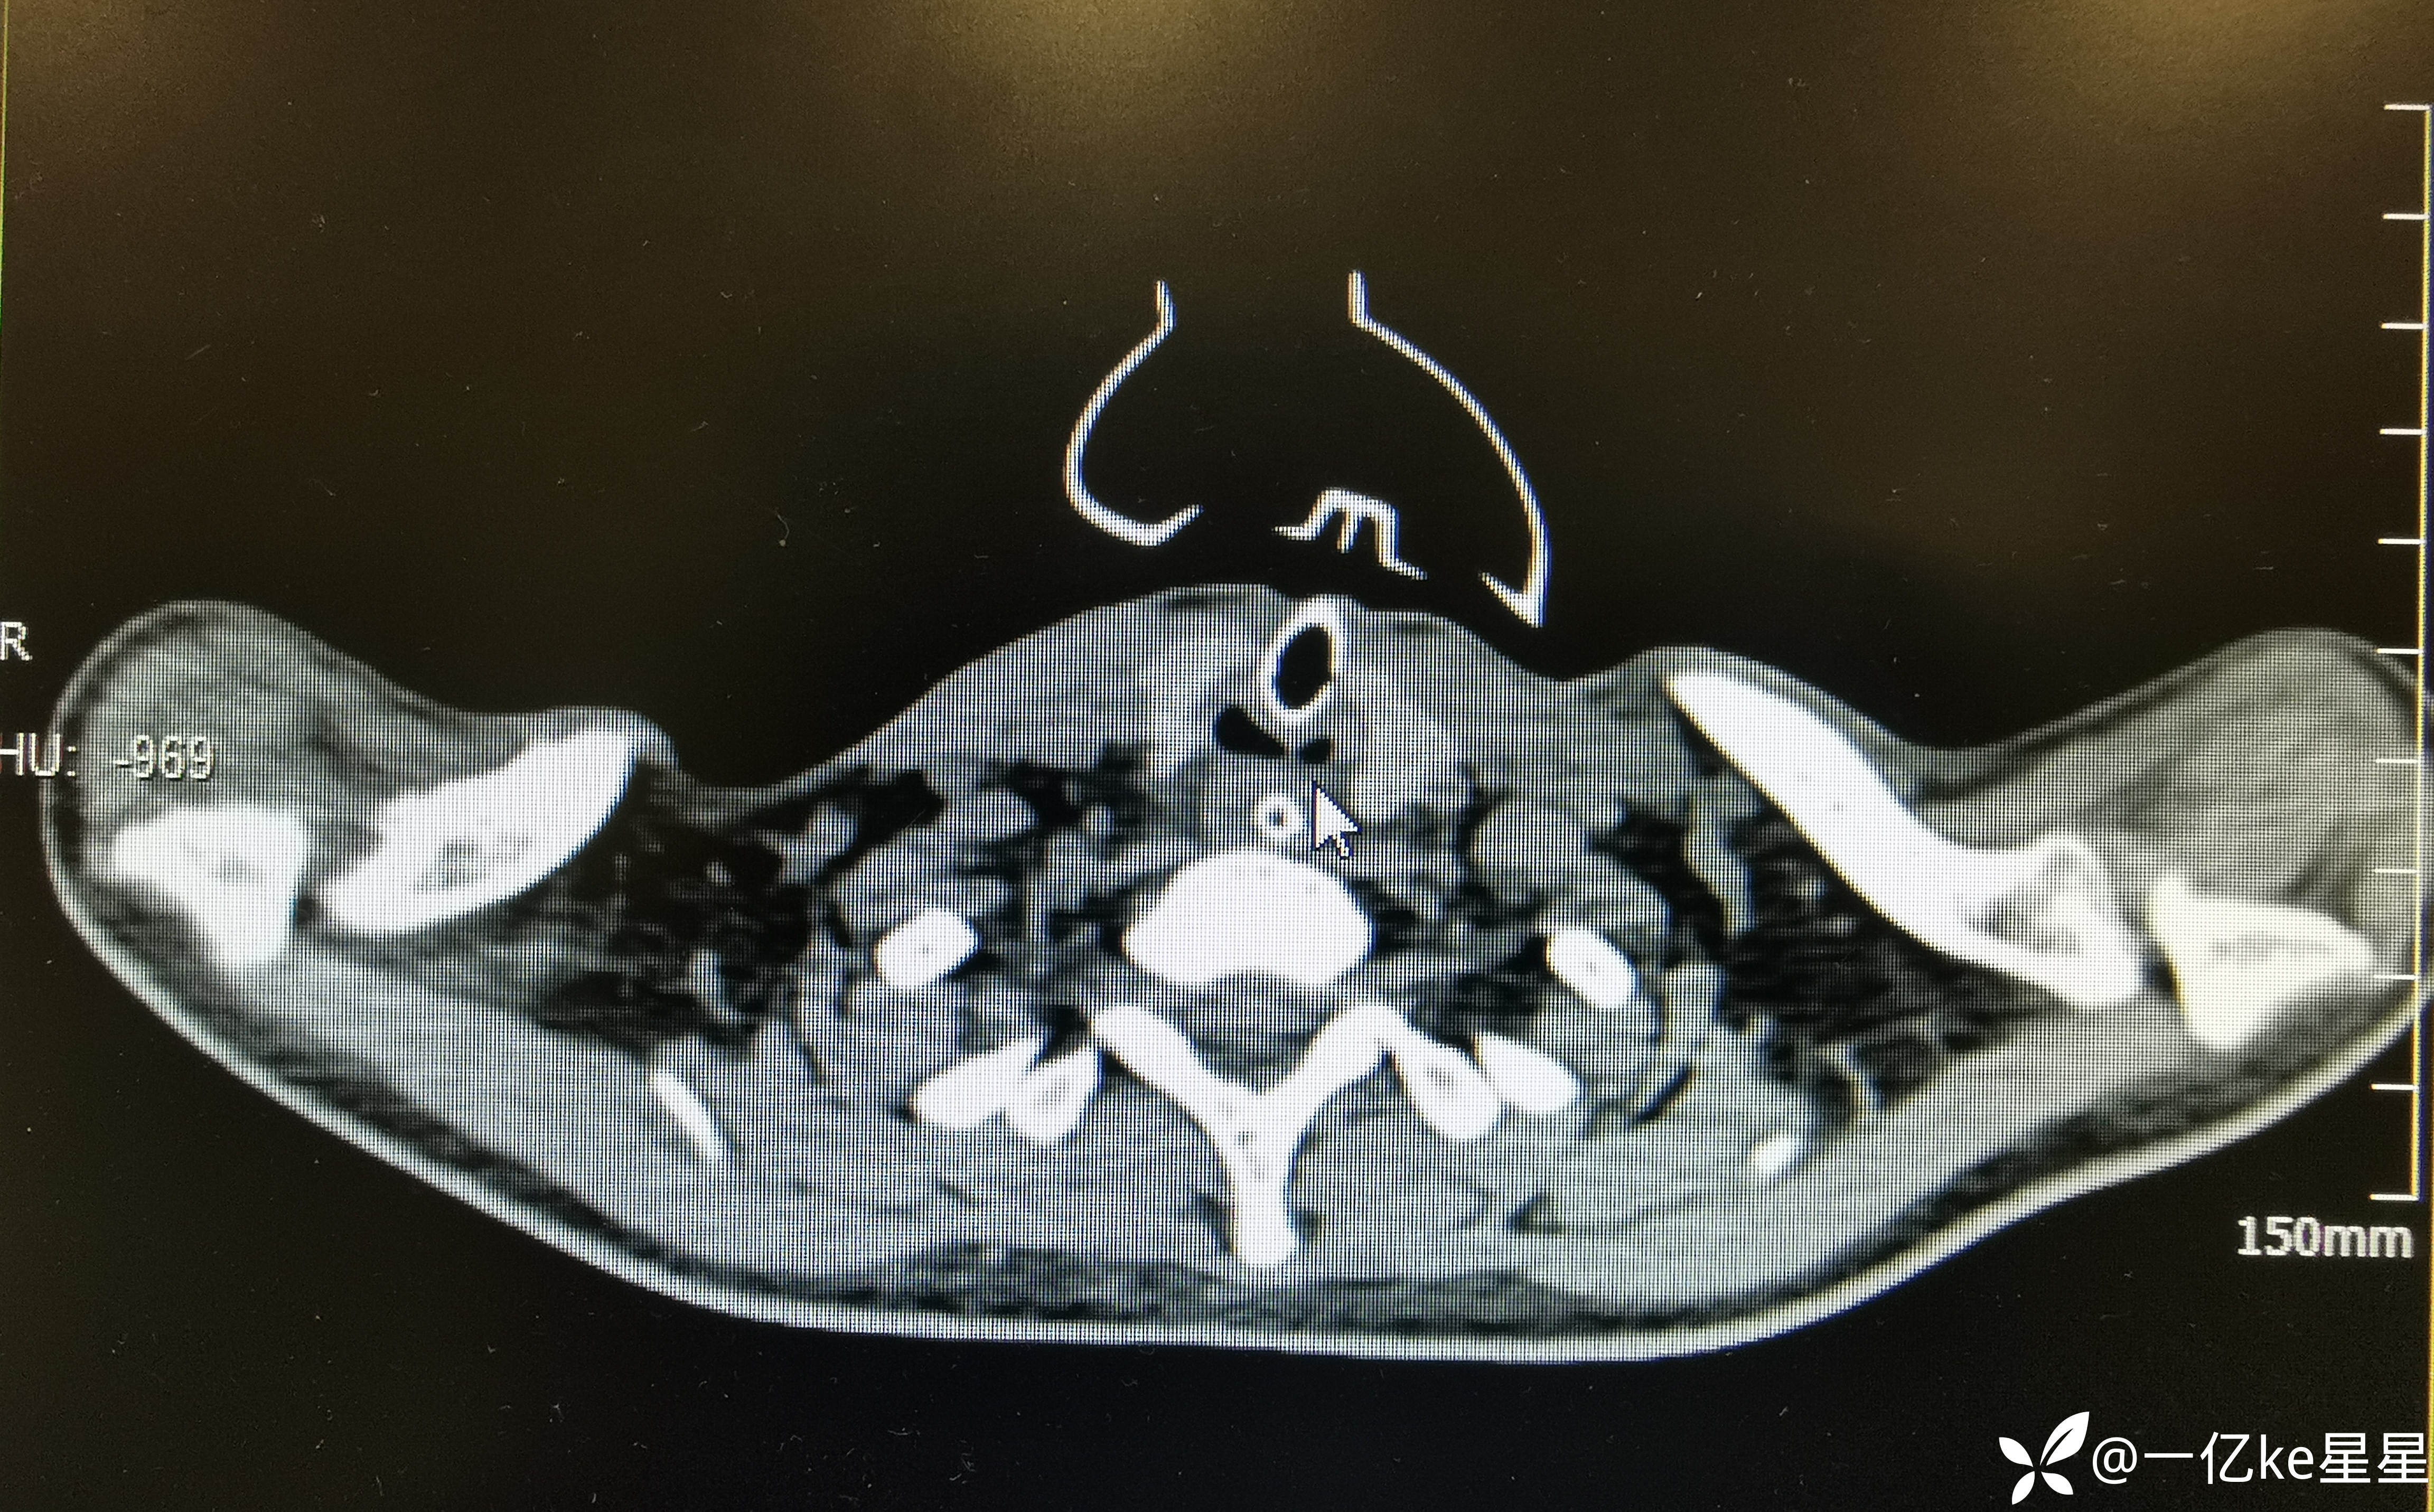

术后给予、抗感染(头孢哌酮舒巴坦钠3g+NS100ml ivgtt q12h)、预防癫痫(左乙拉西坦0.75g 管饲 bid、雾化(乙酰半胱氨酸)、胞磷胆碱胶囊2粒 tid、单唾液酸四己糖神经节苷脂钠注射液40mg+NS100ml ivgtt qd、补液、高压氧治疗、康复训练等治疗,患者意识状态好转,患者神志清(2023.11.30),拟拔除气管插管,间断堵管约2小时后,患者出现喘憋不适,氧饱未见明显降低,完善胸部CT(2023.11.28):考虑存在气道狭窄

进一步完善支气管镜检查: